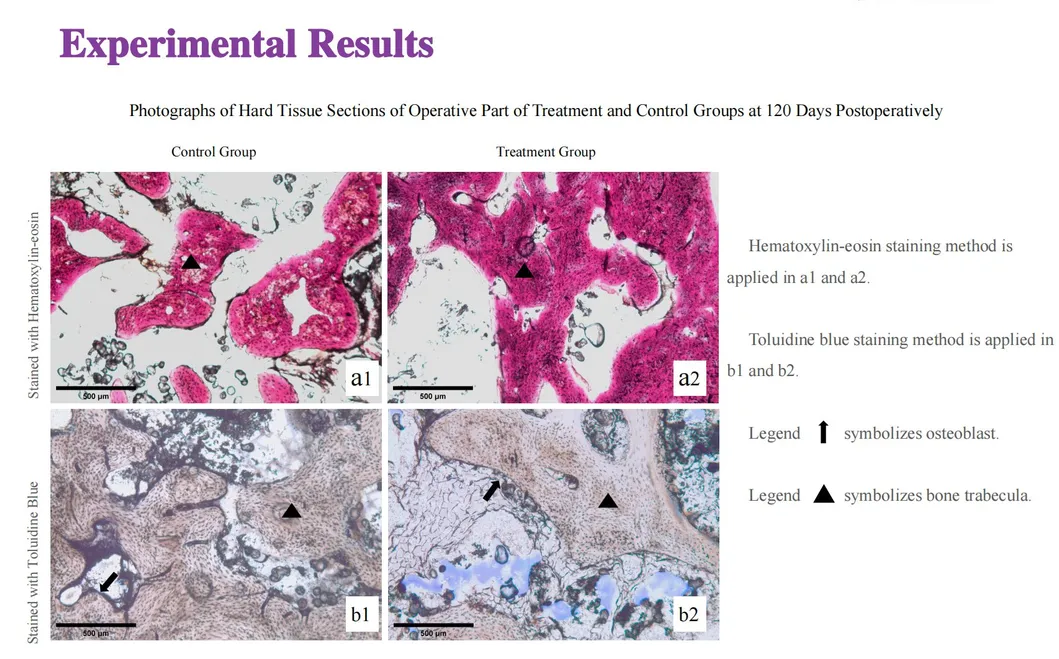

In this groundbreaking study, dogs were selected to assess the effectiveness of the Golden Cudgel-Pneumatic Dental Elevator Kit. Researchers meticulously documented physiological parameters, extraction duration, and socket damage compared to traditional manual devices. The data provides profound insights into the superior performance and efficiency of these advanced dental tools.